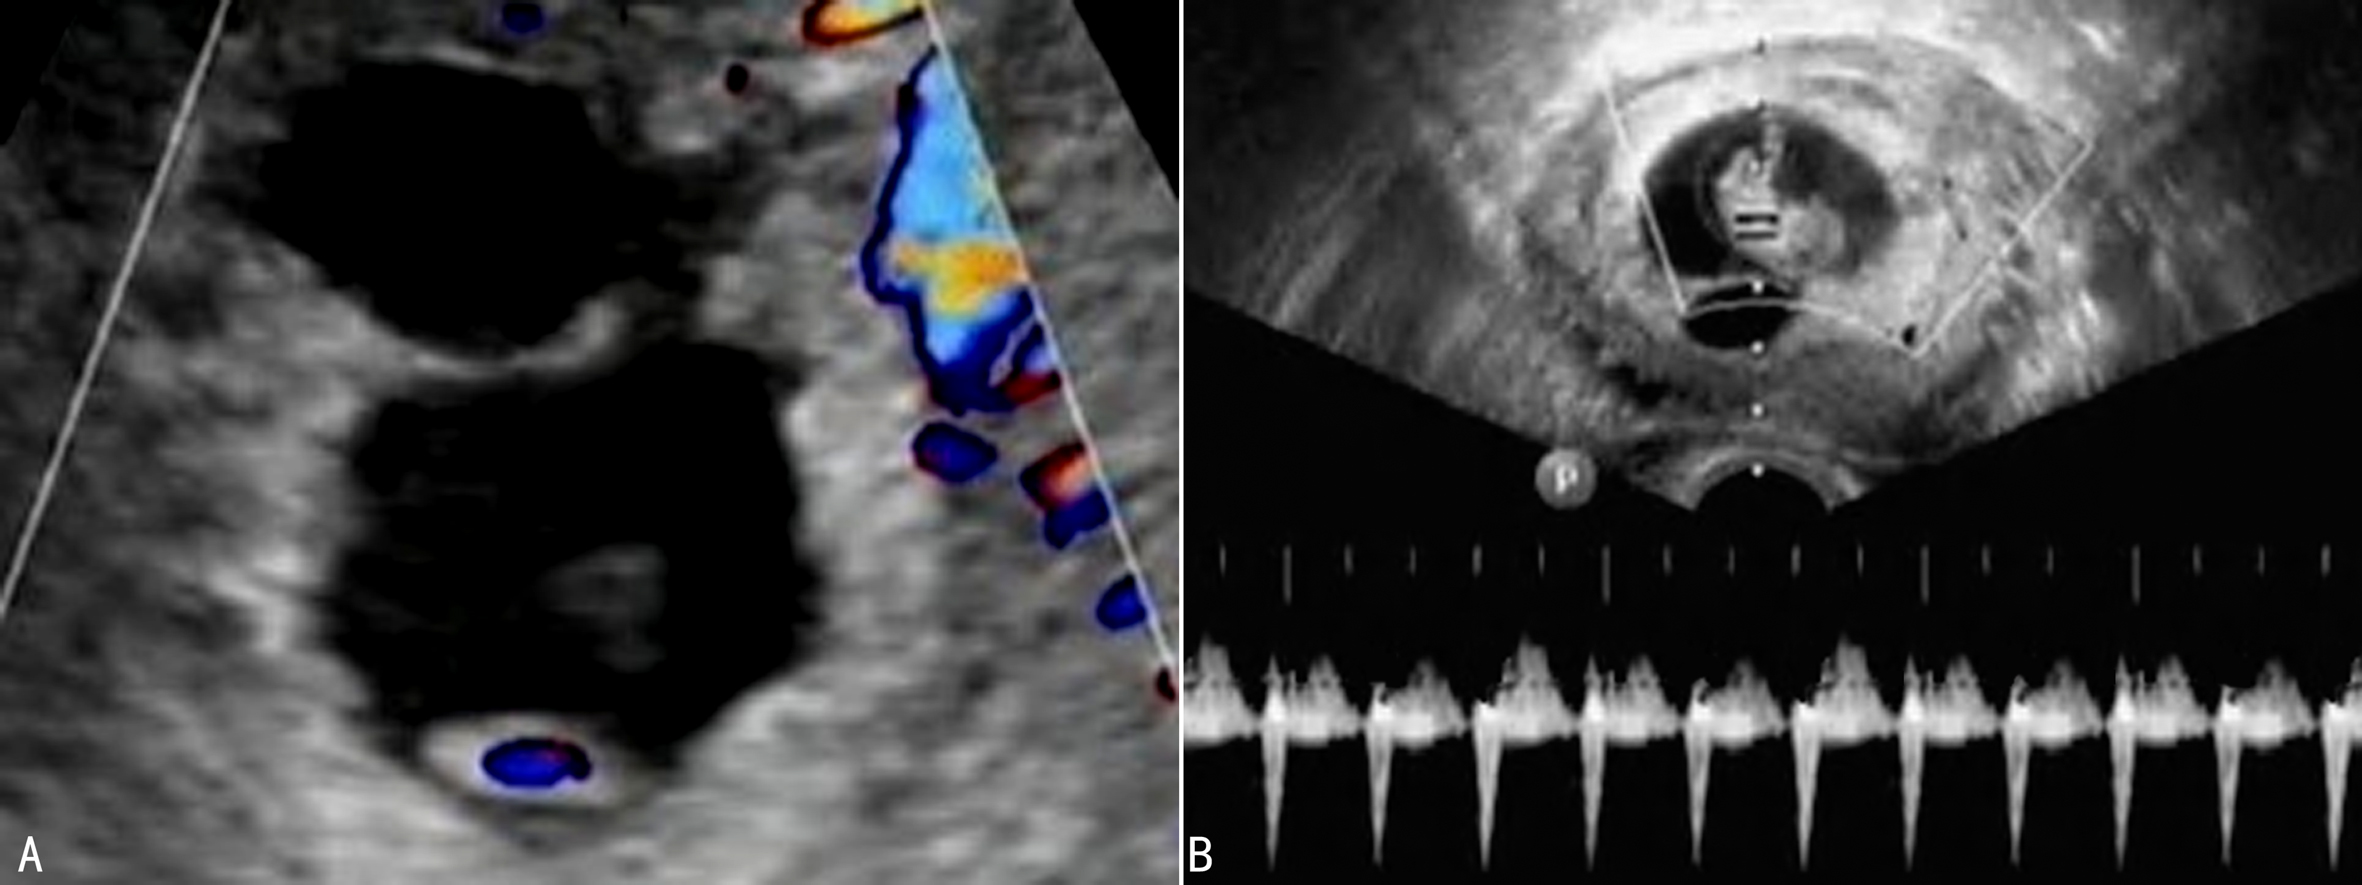

1.妊娠囊 妊娠囊的计数是早期诊断多胎妊娠的基础。早期妊娠超声显像检查妊娠囊回声及其评价方法可采用同单胎妊娠。TAU于停经后第6周或TVU于第5孕周即可显示妊娠囊(图1A)。需要注意的是早期妊娠显示的单胎妊娠或多胎妊娠可能会有一定的误差,有报道在孕6周以前有11%(24/213)的双绒毛膜囊双胎妊娠和86%(6/7)的单绒毛膜囊双胎妊娠被诊断为单胎妊娠。

超声检查显示的分离的妊娠囊个数即为绒毛膜囊个数(图1B),两个妊娠囊则提示双绒毛膜囊双胎妊娠,三个妊娠囊即提示三个绒毛膜腔。停经10周时羊膜腔扩大、绒毛膜逐渐变薄,羊膜与绒毛膜融合,超声显像检查对绒毛膜特性评估的难度明显增加。

图1多胎妊娠声像图 A:TVU显示两个孕囊 B:TVU显示5个孕囊